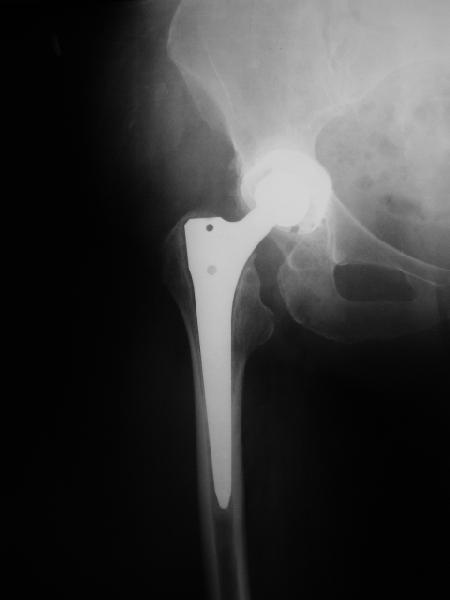

Нестабильность протеза?

В наше отделение обратилась больная (родственница одного из сотрудников) 1948 г.р. В 2002 г. тотальное эндопротезирование тазобедренных суставов в Кургане.

Все было благополучно до 22 апреля этого года, когда при развороте на фиксированной стопе появилась резкая боль в правом тазобедренном суставе и верхней трети бедра. Конечность стала неопорной. Активные движения - резко болезненны. Пассивные - свободные, безболезненные. Местно - есть зона гиперемии в вертельной области. Пальпаторно - флуктуация (гематома?) по задне-наружной поверхности бедра. Температура субфебрильная. Больная сейчас на постельном режиме, двигаться, а тем более вставать отказывается из-за боли. Снимки прилагаются. Больная обращалась в клинику эндопротезирования Уральского НИИТО, ей было отказано даже в консультации.

Вопросы - обязательна ли ревизия протеза? В условиях нашей больницы организовать ревизионное протезирование проблематично. Есть ли возможность и на каких условиях можно вновь попасть в Курганский институт?

И про ближайшие дни - надо ли пунктировать область флуктуации? Назначить ли антибиотики? Еще какую-то медикаментозную терапию? Какие-то другие меры?

24 апреля 2005 г. правый сустав фас (тут и болит)

24 апреля 2005 г. правый сустав профиль (тут и болит)